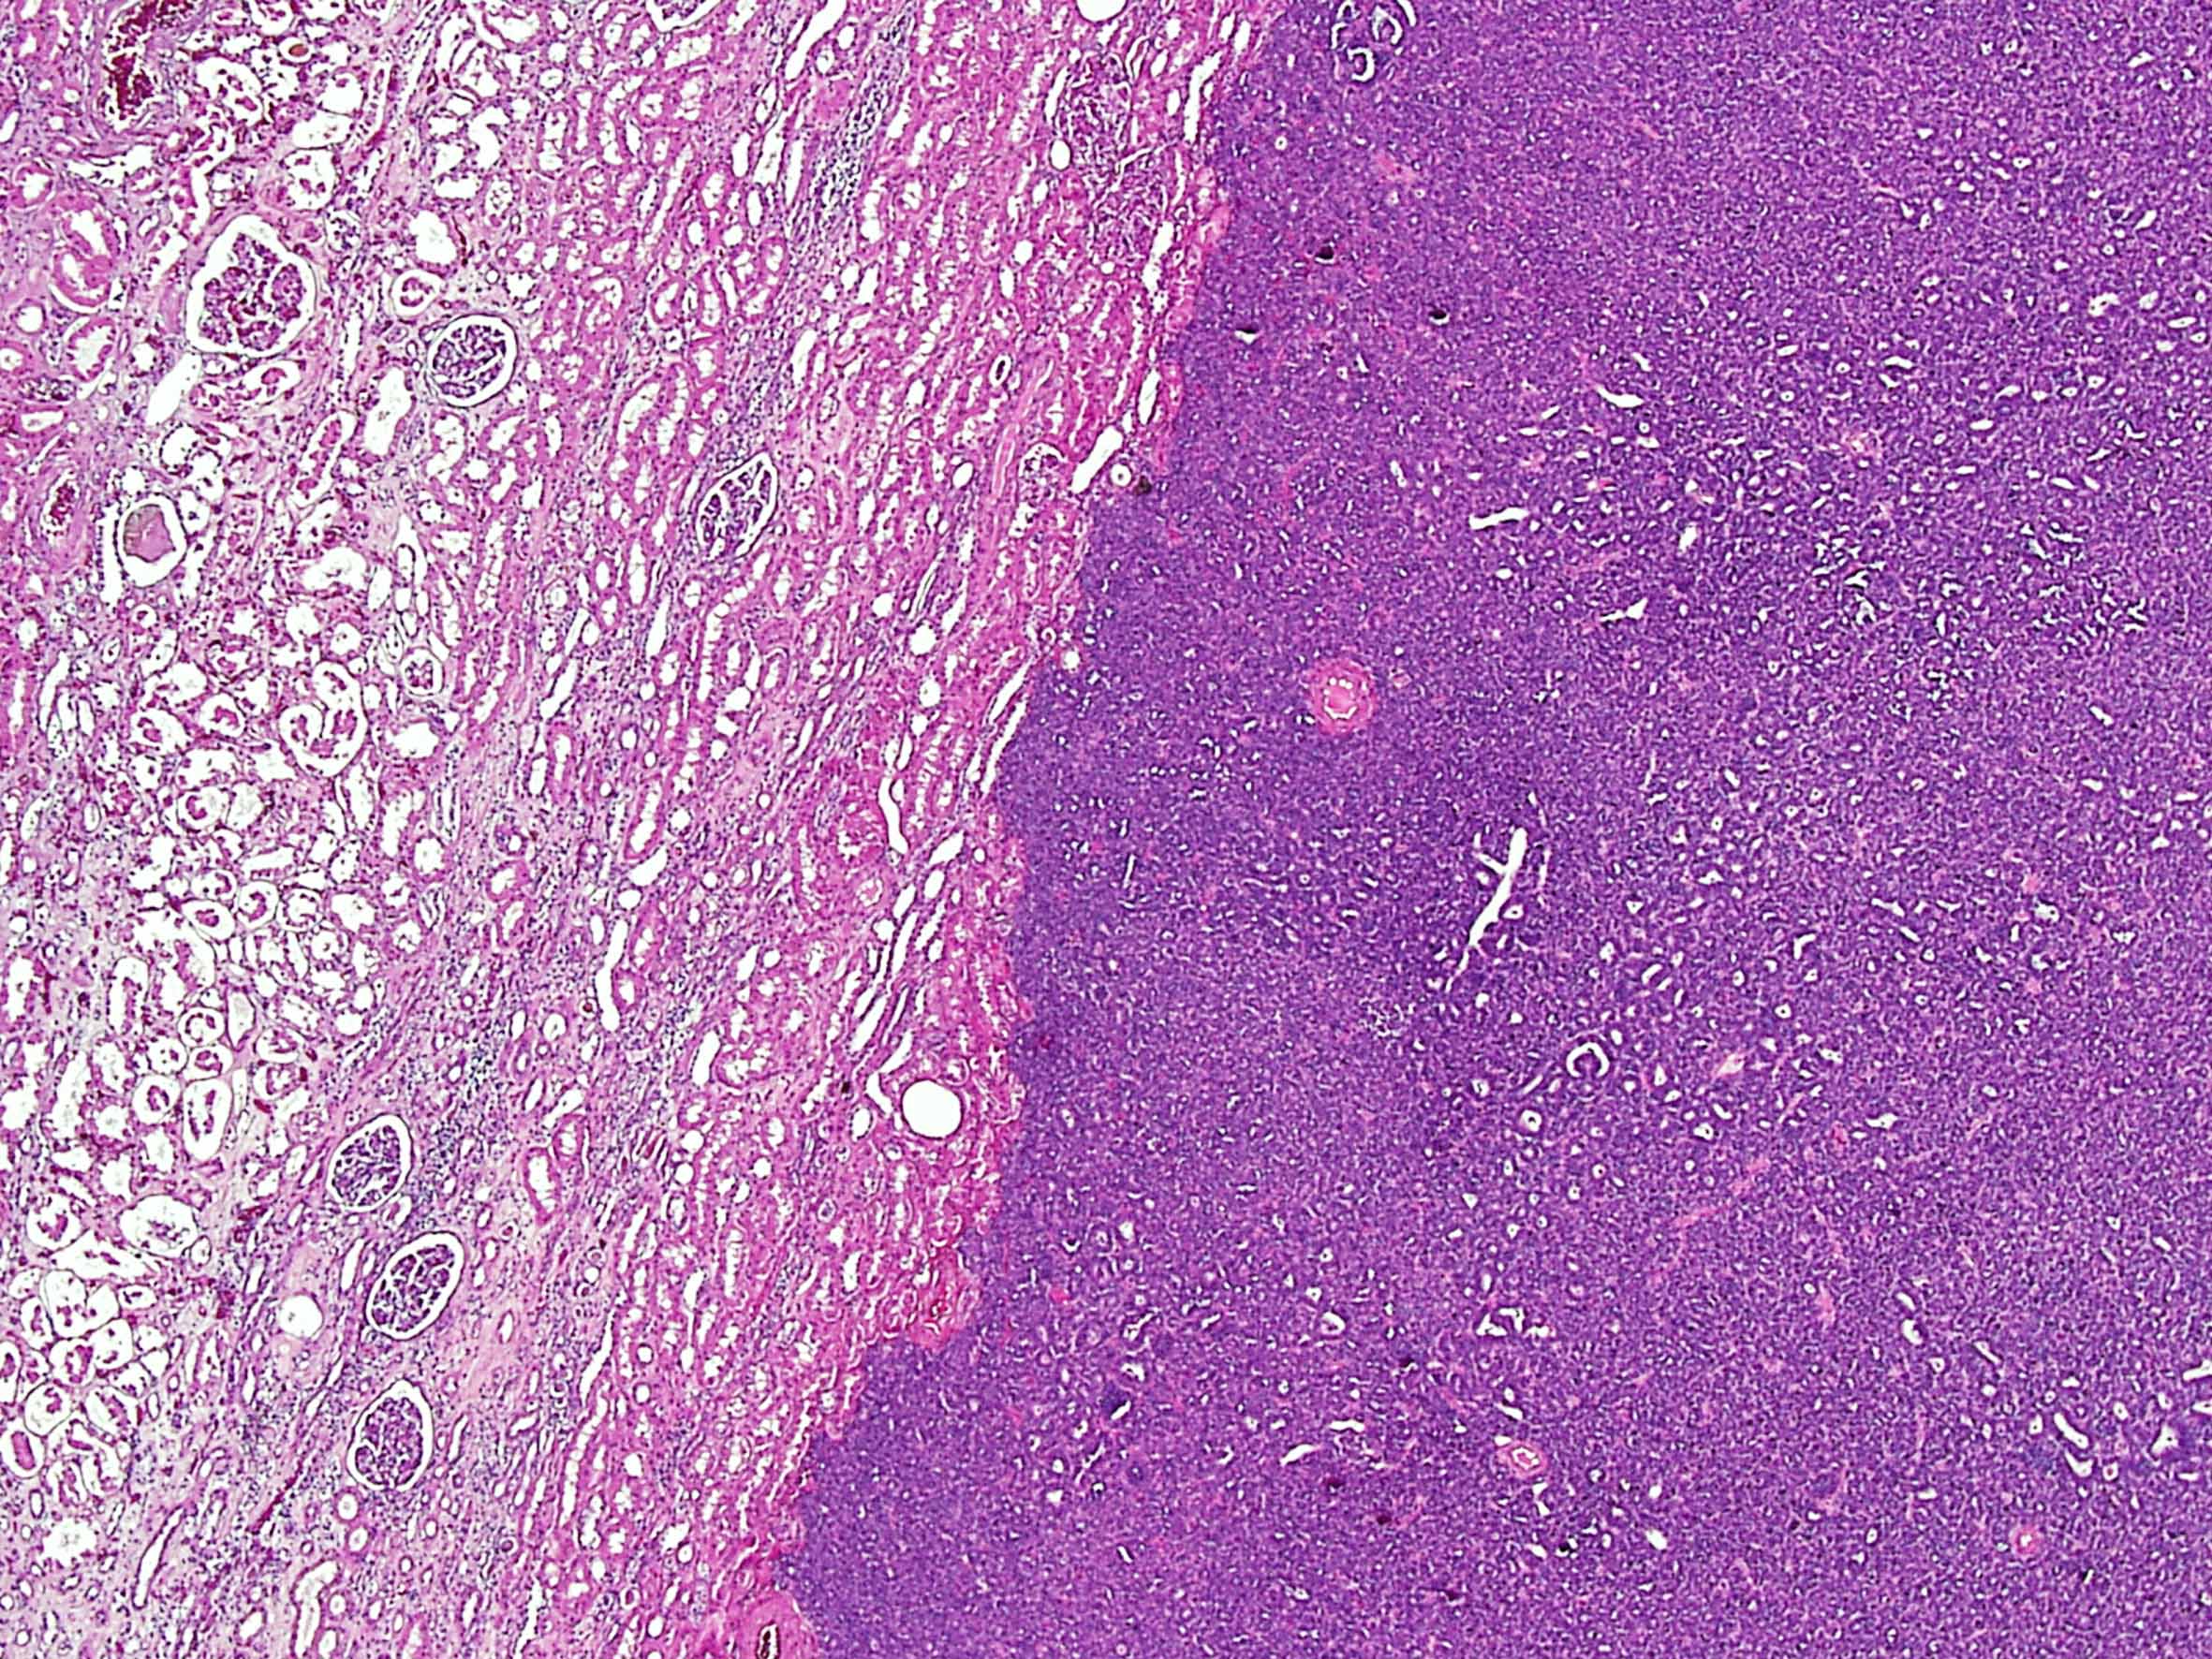

Case description (by case creator):

Metanephric adenoma